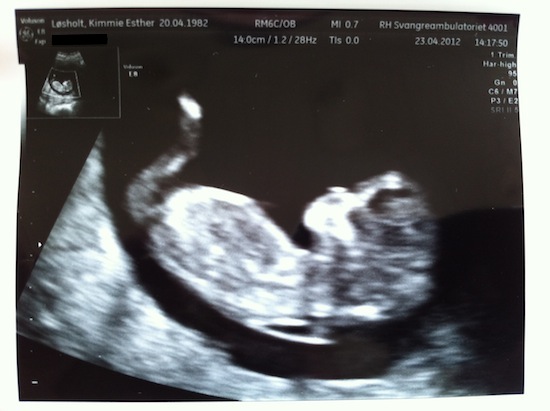

Kimmie og jeg var i går til nakkefoldsscanning og fik der gode nyheder. Kimmie havde afgivet en god blodprøve, har en god alder og scanningen viste en lille nakkefold, hvilket tilsammen gav os det bedste resultat vi kunne ønske.

Så nu tør vi endelig sige det: Vi skal være forældre!

3. scanning 3. scanning - 23. april, 51,5mm